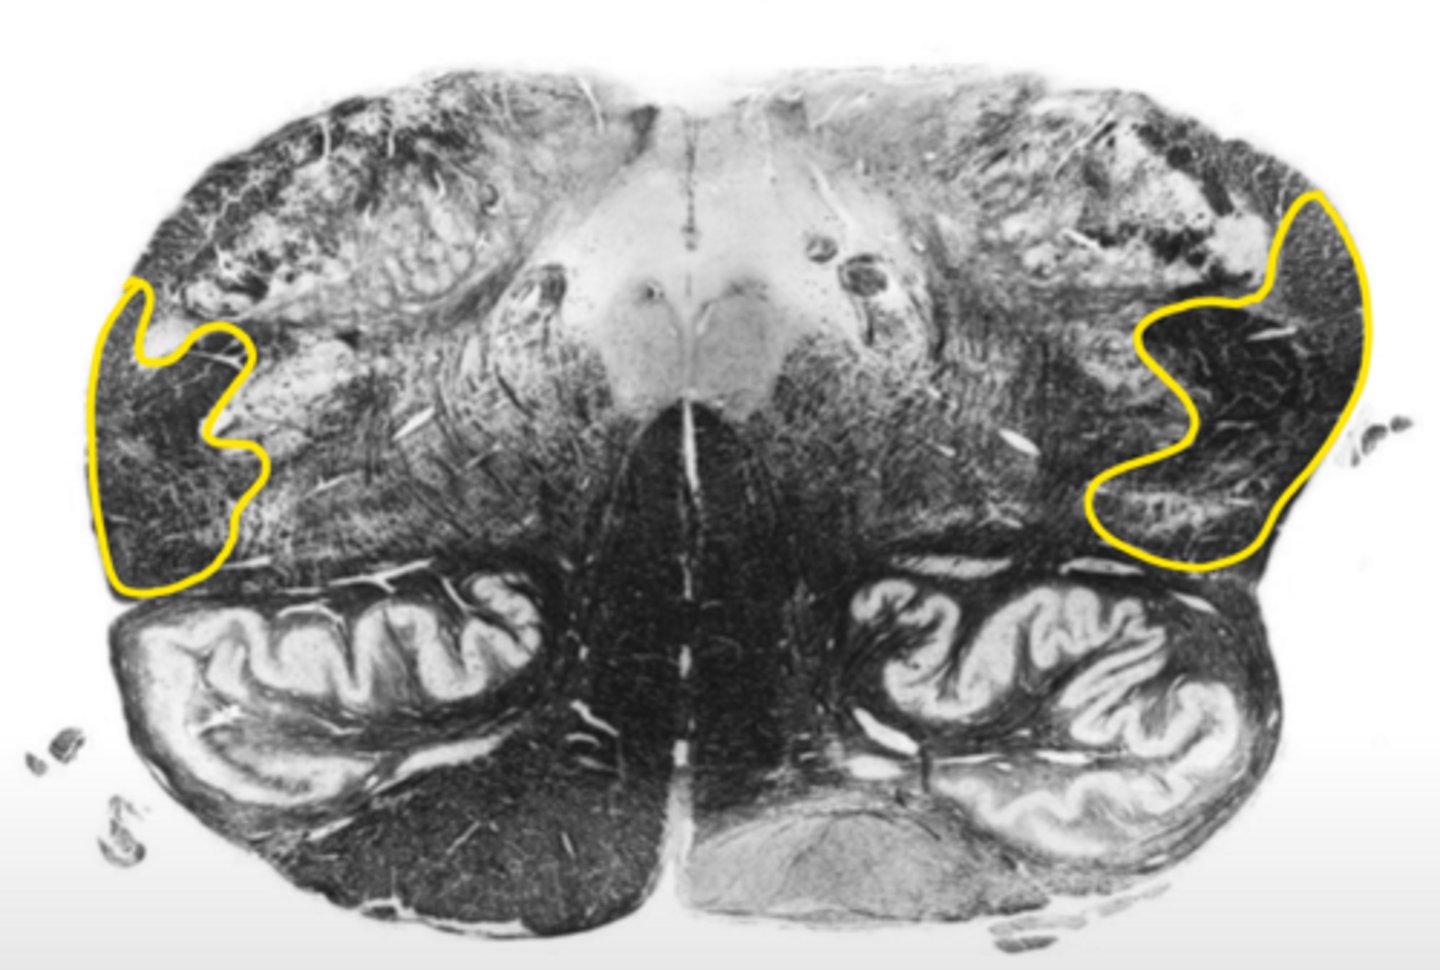

hypoglossal nucleus

ID the nucleus

vestibular nucleus

inferior cerebellar peduncles

ID the structure

reticular formation

vagus nerve

ID the nerve

principle olivary nucleus

corticospinal fibers

hypoglossal nerve

medial lemniscus

anterior median sulcus

open medulla

ID the brainstem level